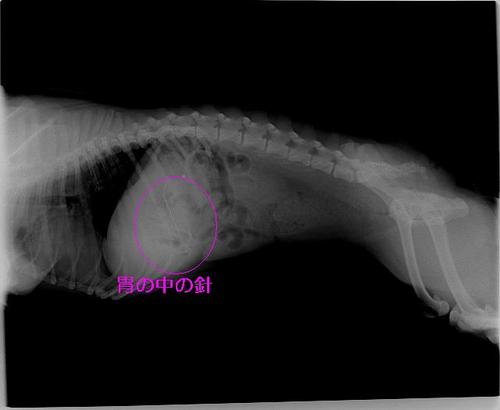

「ぬいぐるみを作っていたのですが、この時に使っていた針を飲み込んだかもしれません!」と言う事であるワンちゃんがいらっしゃいました。すぐにレントゲンを撮っておなかの中を調べてみると・・・

Img6576.jpg